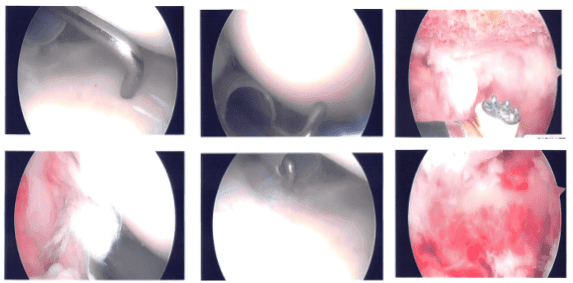

No hubo daños. Se tomaron y guardaron fotos. El artroscopio fue introducido en el espacio subacromial. Hubo bursitis subacromial, que fue desbridada. Había sangrado y dificultad debido al peso y tamaño del paciente.

Se introdujo un implante grande de Regeneten a través del portal lateral y se colocó con el uso de tachuelas de PLA x8. Se tomaron y guardaron las fotos finales. El hombro fue completamente irrigado y drenado.

Foto intraoperatoria